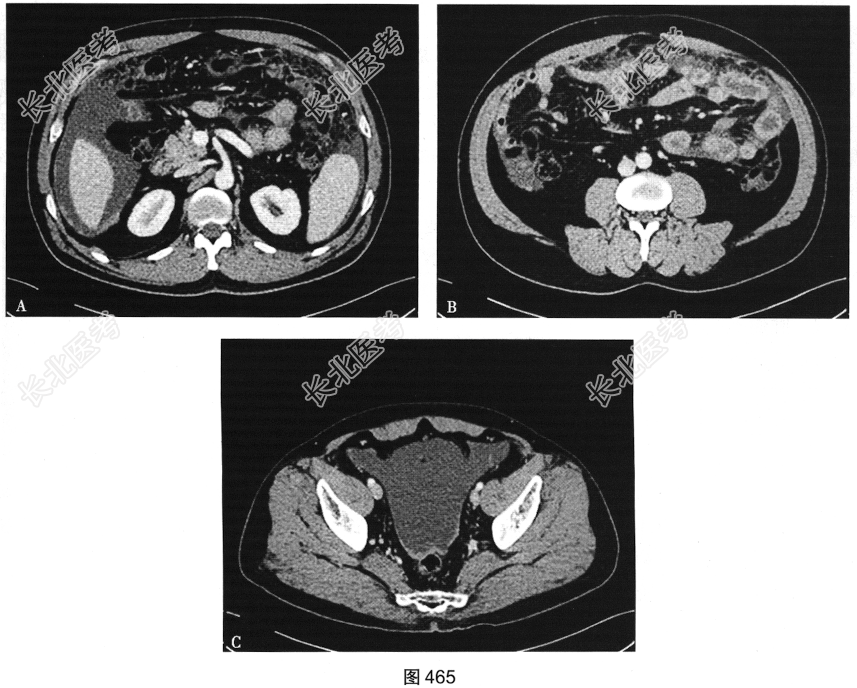

患者女性,40岁,卵巢癌术后1年,常规复查。行腹部CT检查,如图465所示。

- 多项选择题1.初步考虑诊断为( )

A、肾脏转移

B、局部复发

C、腹膜转移

D、未见转移

E、肝脏转移

F、脾脏转移

G、骨转移